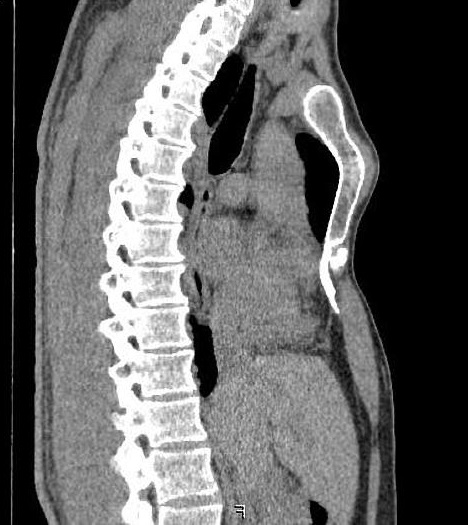

Image radiologique TDM en

coupe axial de aplasia du muscle pectoralis majeur

gauche d'une syndrome de Poland |

Même cas en coupe axiale TDM

fenêtre mediastinale . |

Et en fenêtre parenchymateuse ... |